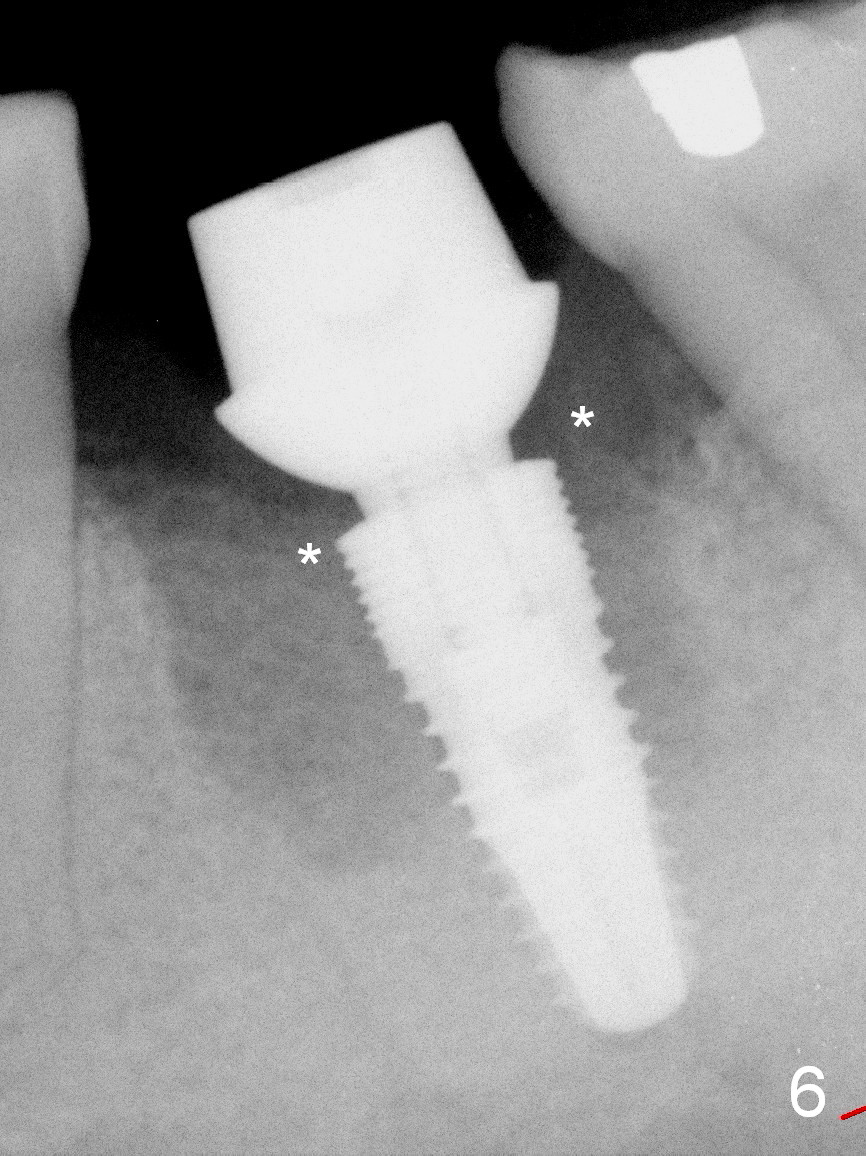

A 37-year-old lady (MP) presents to clinic with chief complaint of bad smell from lower right crown (Fig.1: #19; red dashed line: superior border of the Inferior Alveolar Canal). One of the most prominent pathologies is fracture of the distal root (<). After extraction, the socket is treated with 2% Xylocaine/1:50,000 Epinephrine. The coronal distobuccal plate is defective. Osteotomy is initiated as lingual as possible. The 1st intraop PA shows that the osteotomy is shallow and distal to the almost non-existent septum (Fig.2 S). The osteotomy is intended to move more mesially, but the result is not obvious when 4.5x14 mm drill is in place (Fig.3 D). The depth of the osteotomy is increased by 3 mm; a 5x17 mm tap is stable (Fig.4 T). A 5x12 mm implant (Fig.5 I) is placed until it cannot be turned. The implant is higher than the distal crest (^). In addition there is space apical to the implant (Fig.5*). After 5 mm drill is used, the implant is seated deeper with insertion torque < 35 Ncm (Fig.6). It suggests overprep. Anyway, an immediate provisional is fabricated after placement of an abutment (A). After reline, the provisional fits well. It has to be removed with forceps for occlusal adjustment. Finally the abutment/implant complex turns in the socket with fingers. The rotation/position of the complex is randomly adjusted. When the provisional is cemented, it does not seat completely, but is stable. If the implant osteointegrates, the provisional must play a role in stabilizing the implant. Bone graft is placed in the gap prior to cementation (Fig.6 *).

When the patient returns 1.5 months postop, the provisional has been fractured (Fig.8 lingual view). The abutment is loose. Intraop analysis of a PA shows existence of the peri-implant defect (Fig.7). When the abutment is removed, the implant is found to be stable. As a new smaller abutment (Fig.9: 6.8x4(3) mm) is being torqued at 35 Ncm, the abutment/implant does not turn. Impression for final restoration is taken. Postop analysis of PAs in Fig.6,7 shows that the peri-implant defect has been reduced in 1.5 months. Immediately postop, the fourth coronal large thread is buried in the solid bone, whereas 1.5 months postop the third thread appears inside the base bone.